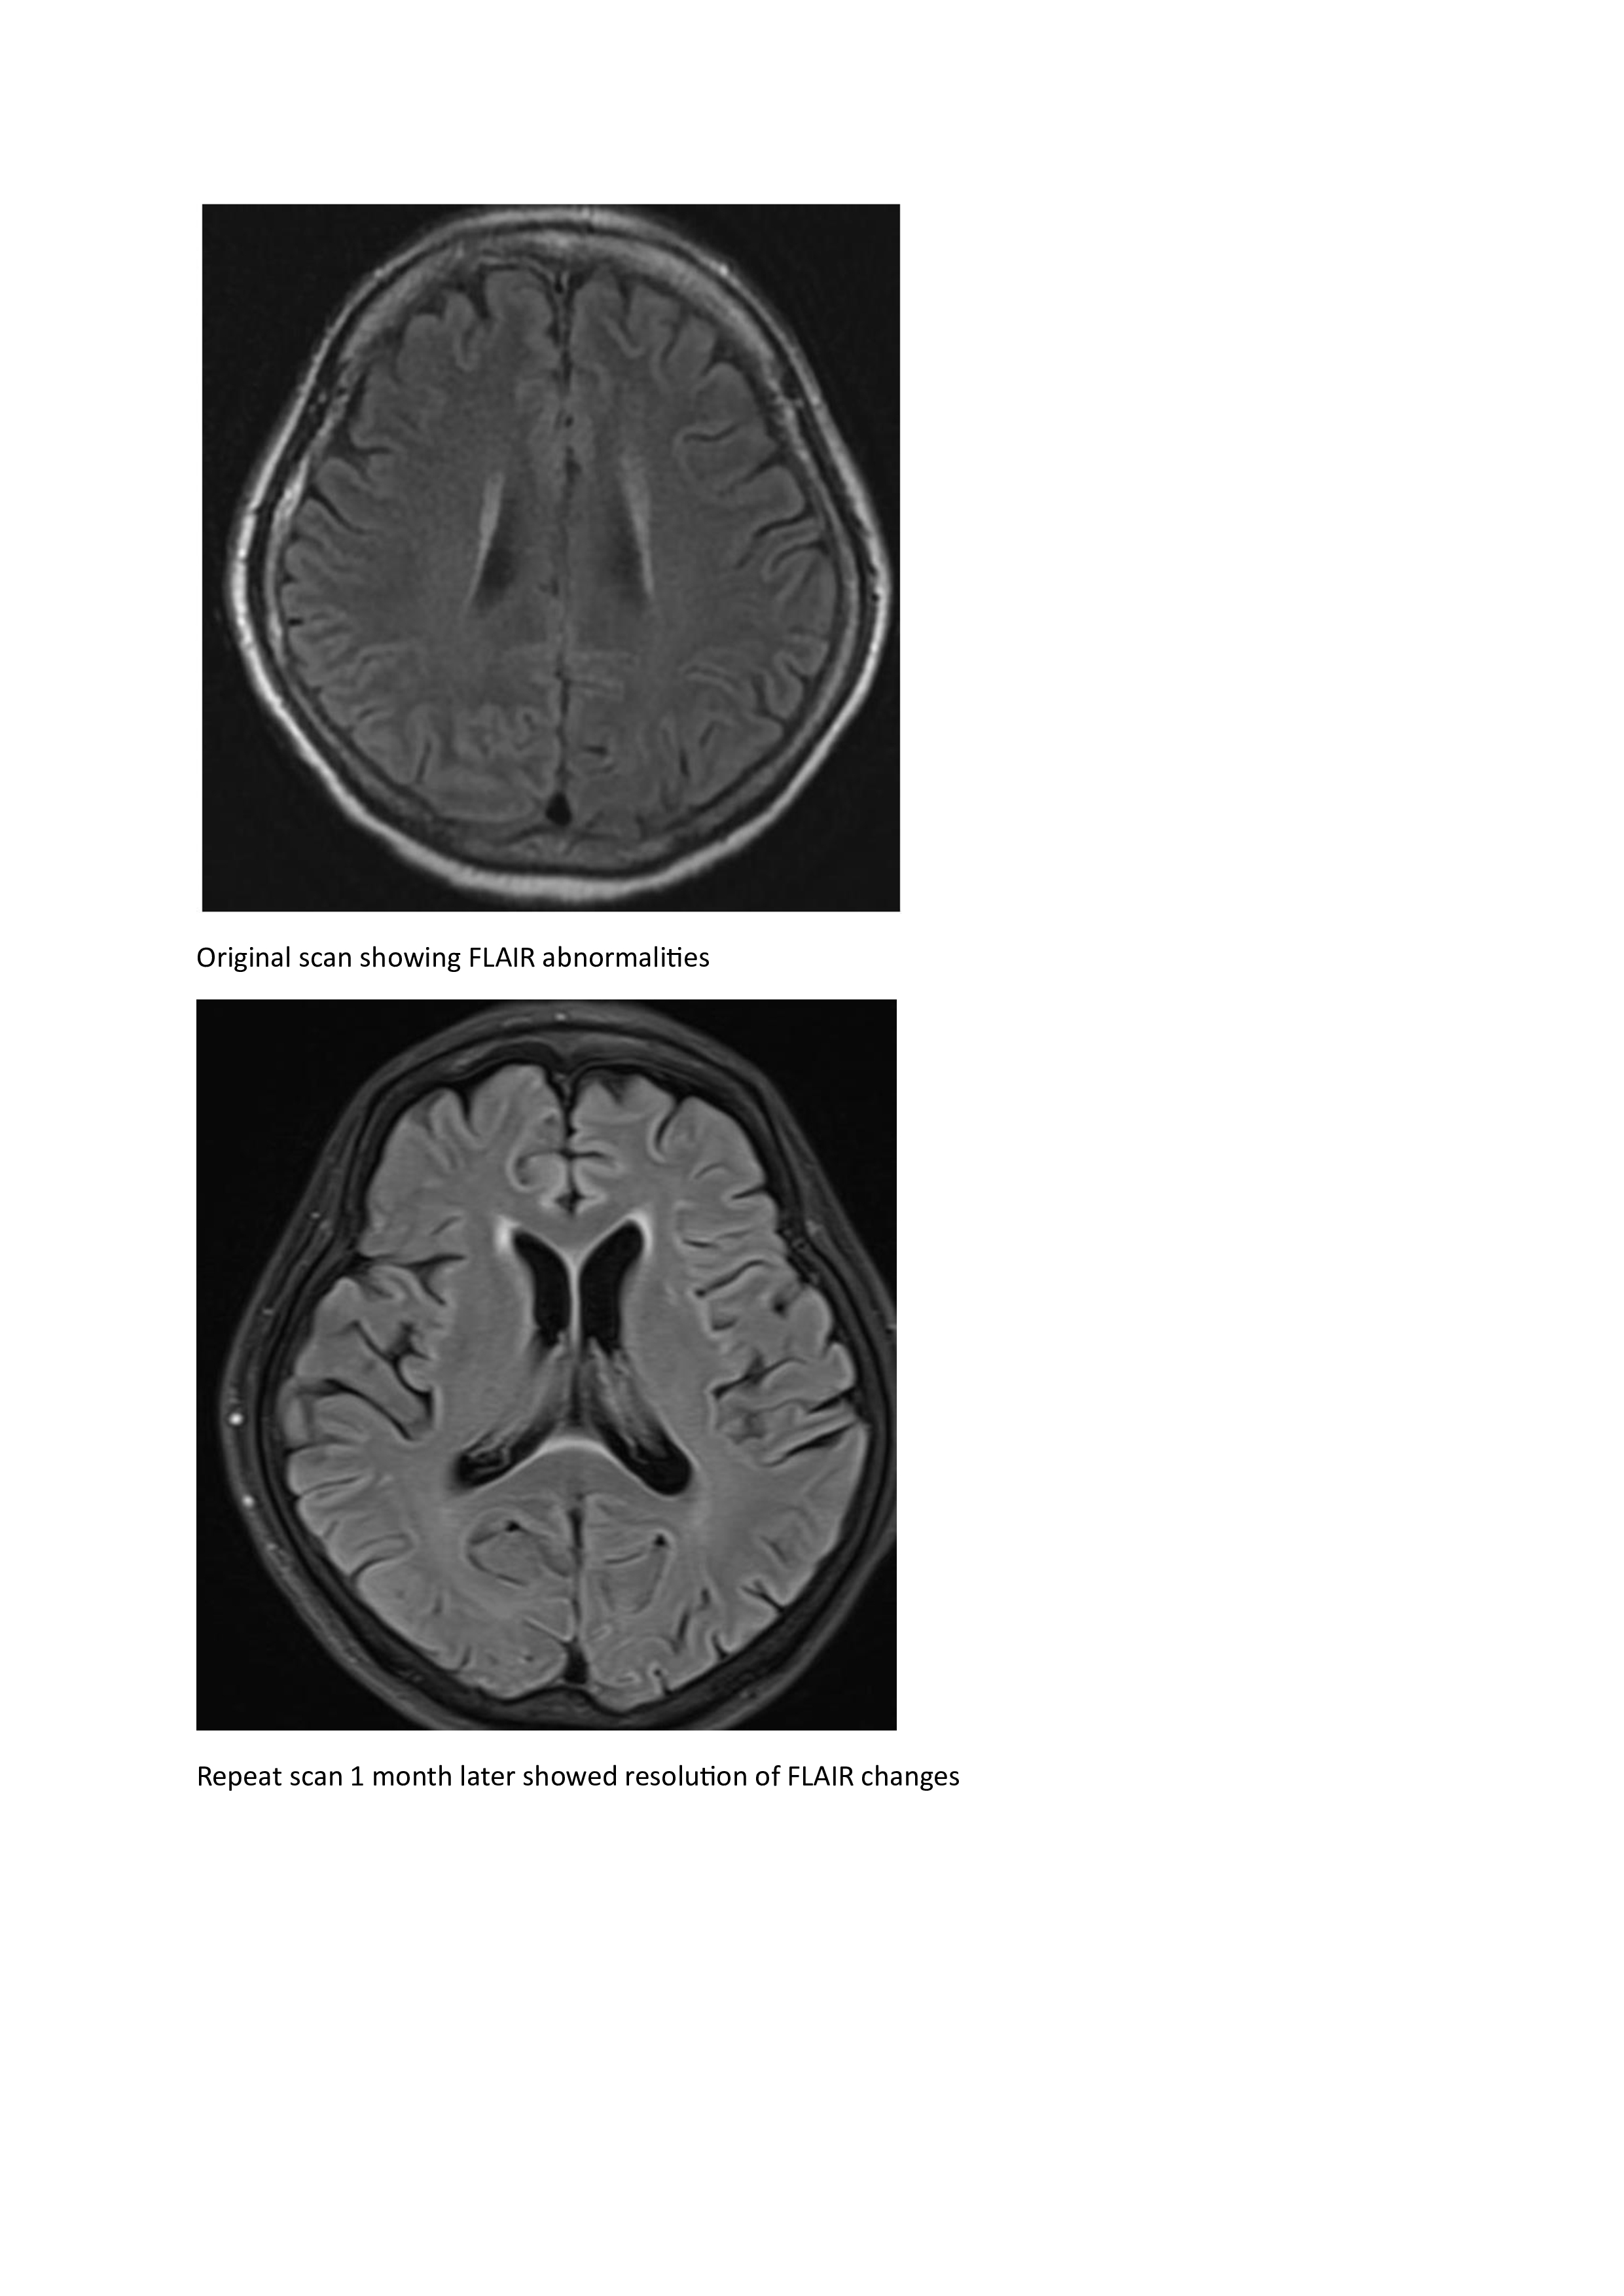

Results:

A 67-year old woman with chronic hypertension, hyperlipidemia and diabetes mellitus non-compliant to medication presented with a 10-day history of recurrent visual phenomena in the left visual field. She described stationery multi-coloured flashing lights which decreased in intensity, brightness and size after 3 minutes. She was alert and conscious during attacks. There was no limb jerking. Neurological examination was normal with no visual field defect. Capillary glucose was 28.1 mmol/L, Hba1c 9% and B-hydroxybutyrate < 0.1. She was treated with actrapid 8 units, glipizide 5 mg BD and empagliflozin 12.5 mg OM. Interictal electroencephalogram was normal with no epileptiform activity. Brain magnetic resonance imaging revealed restricted diffusion in the right occipital cortex with corresponding cortical thickening and increased FLAIR signal with subtle hypodensity on GRE sequence. Her visual symptoms improved dramatically with hydration and diabetic control. She was treated with a short course of keppra. One month later repeat MRI brain showed resolution of the DWI and FLAIR abnormalities.

Conclusions:

Visual hallucinations are an uncommon but well recognised and fully reversible complication of HHS. Clinicians should not forget HHS in the workup of occipital lobe.

Initial dwi